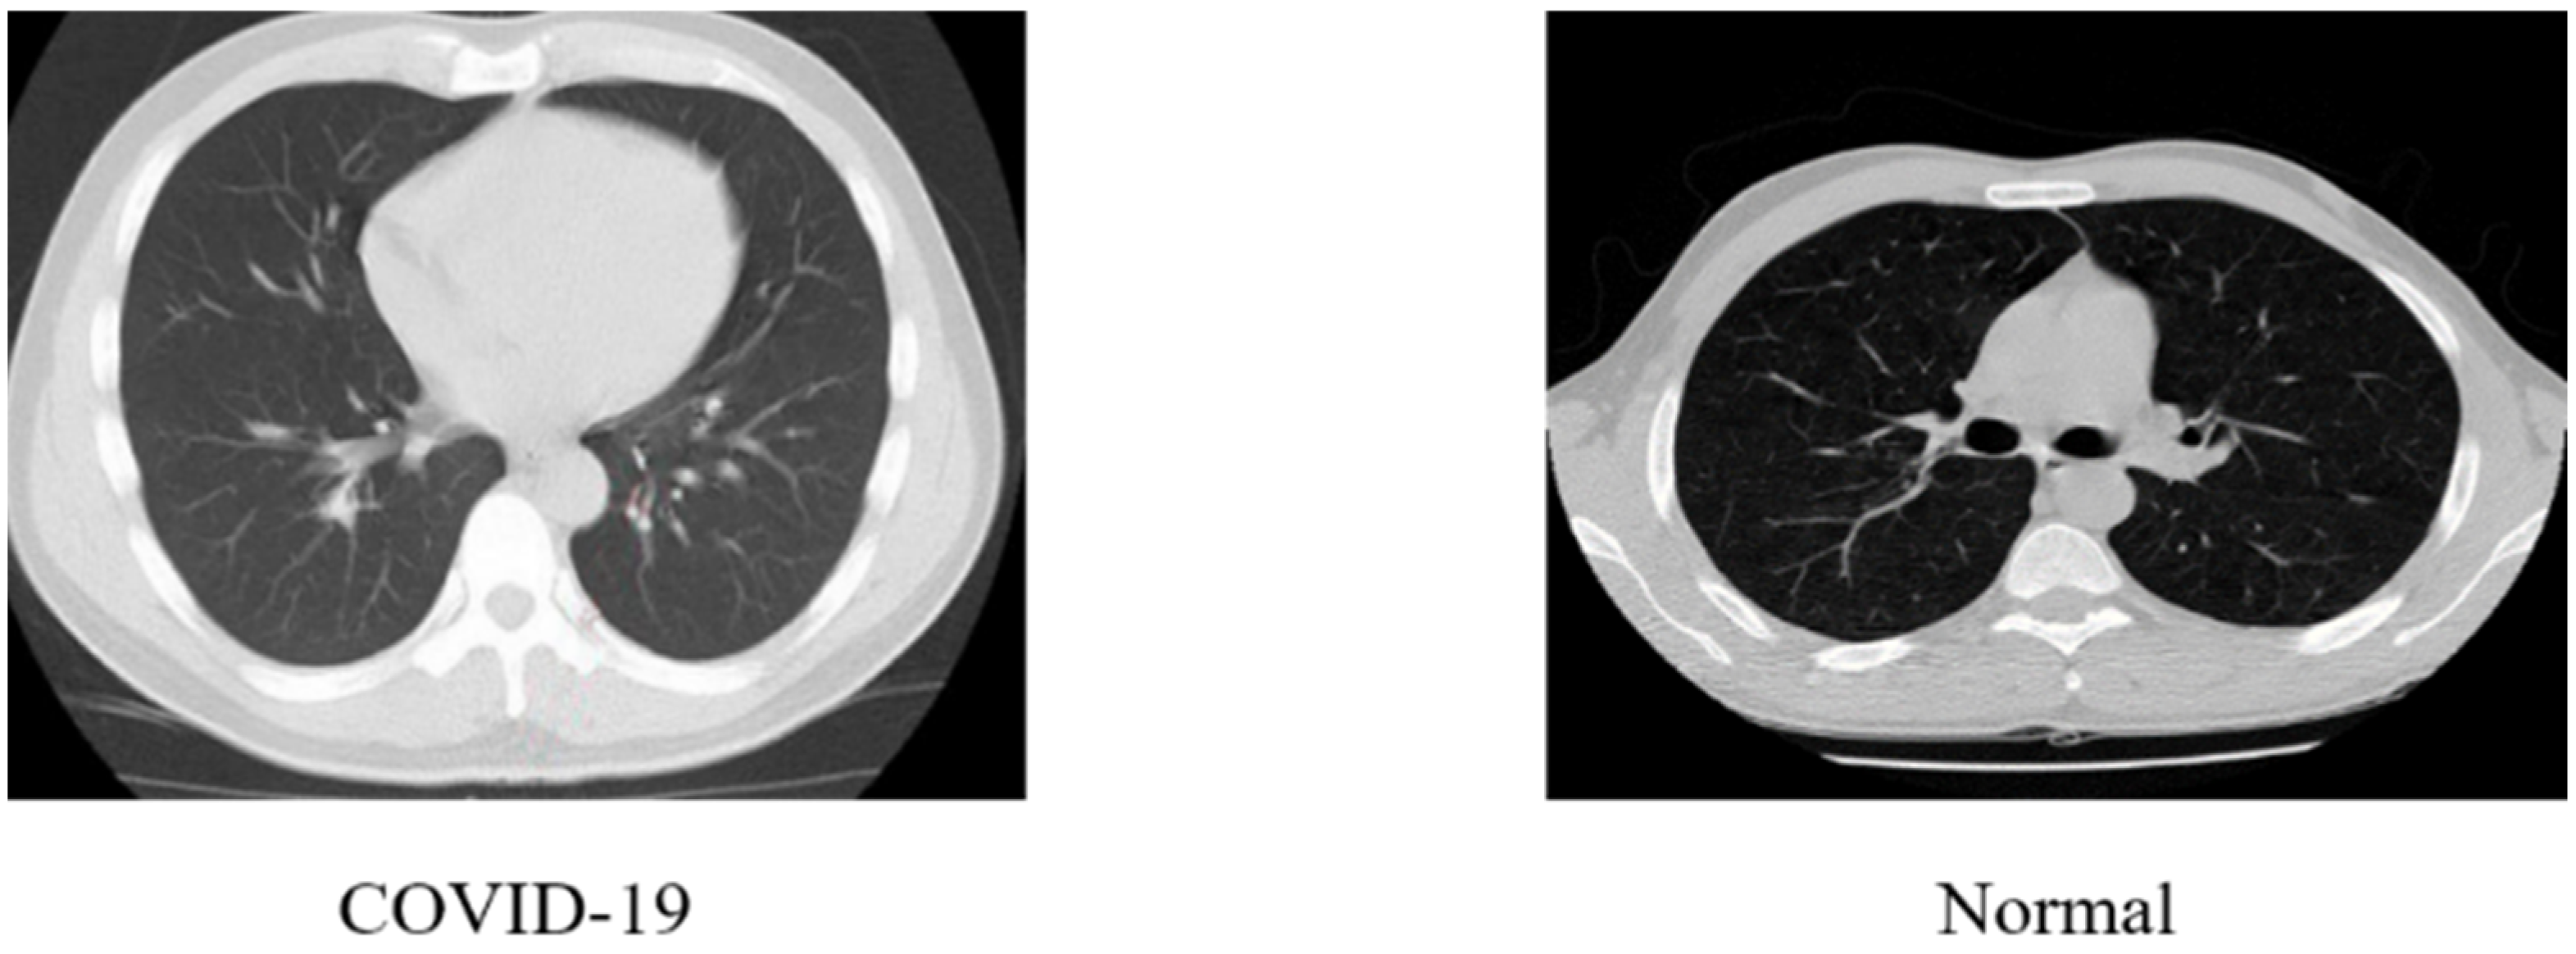

3.1. Dataset Description